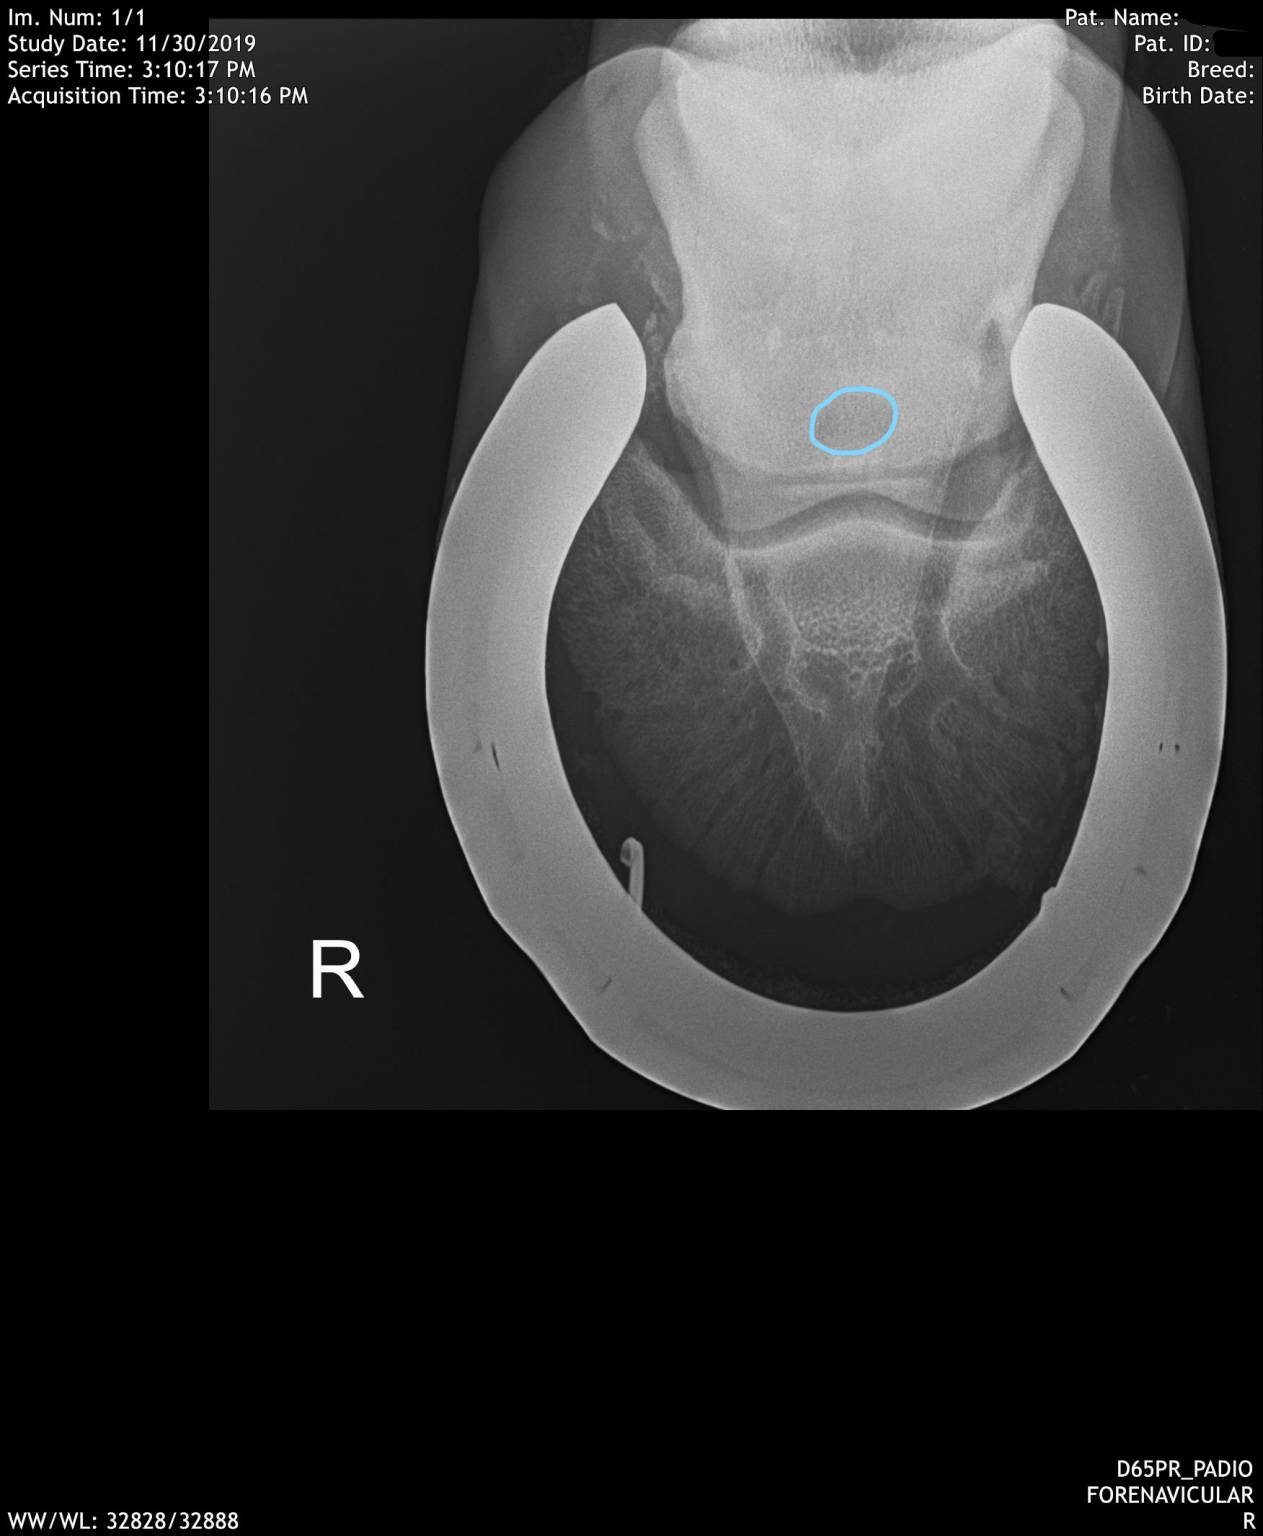

Navicular Bone Radiographs Horse Bone Spur On Navicular Horse The navicular bone is held in position by three strong ligaments. Navicular bone partition is a rare condition reported in horses, which is during the evaluation of a lameness or prepurchase. Navicular syndrome is a degenerative disease complex of horses that can encompass injuries to any of the structures within the navicular apparatus of the foot, including the navicular bone,. Bone Spur On Navicular Horse.

December Navicular Cyst Swiftsure Equine Bone Spur On Navicular Horse Navicular bone partition is a rare condition reported in horses, which is during the evaluation of a lameness or prepurchase. Horse now shod with raised heels/short. The navicular bone is held in position by three strong ligaments. The paired suspensory navicular ligaments originate from the dorsolateral and dorsomedial aspects of the proximal phalanx and attach to the proximal navicular border. Bone Spur On Navicular Horse.

The beat on navicular disease in horses MSU Extension Bone Spur On Navicular Horse The navicular bone is held in position by three strong ligaments. The paired suspensory navicular ligaments originate from the dorsolateral and dorsomedial aspects of the proximal phalanx and attach to the proximal navicular border and both extremities. Xrays show spur on nb probably impeding tendon. Navicular bone partition is a rare condition reported in horses, which is during the evaluation. Bone Spur On Navicular Horse.